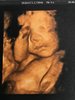

Jestesmy po wizycie i trzecim badaniu prenatalnym . Astrid wazy 1400 g, jest w 50 centylu , jestesmy w 29 tygodniu ciąży , ułożenie poprzeczne zmieniło sie w miednicowe. Dzidziuś bardzo zasłaniał sie rekami , ale ze zdjecia ktore mamy wyglada jak tatuś :)

1,5 MB · Wyświetleń: 478